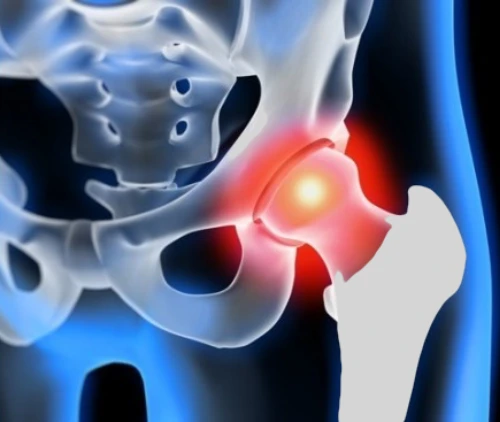

La protesi totale d’anca (Total Hip Arthroplasty, THA) è un intervento chirurgico che sostituisce le superfici articolari malate dell’acetabolo (bacino) e della testa del femore con componenti artificiali. L’obiettivo è ridurre il dolore, ripristinare la funzione e migliorare la qualità di vita.

- Artrosi primaria avanzata con dolore meccanico quotidiano, rigidità, limitazione marcata del cammino.

- Coxartrosi secondaria (esiti di displasia, conflitto femoro–acetabolare, post-traumatica).

- Necrosi avascolare della testa femorale allo stadio avanzato.